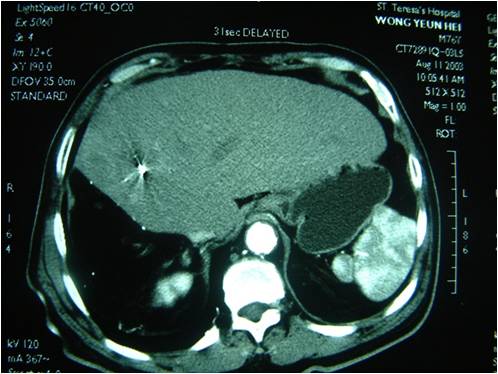

不仅医生要信心,晚期癌症病人自己的信心也非常重要,徐教授讲述了一个号称“漂白水大王”的肝癌病人起死回生的故事:他是香港的一位76岁的企业家王老先生,媒体称为“漂白水大王”,因为他在2003年“沙士”流行期内向社区捐献大量的漂白水。还是在2001年3月份,他因肝癌做了手术,到2003年初时肝癌复发,检查发现肝上已有4个癌瘤。香港医生说无法治疗了。他不屈服,在太太的陪同下来到广州复大肿瘤医院。第二天,他在美国和香港的6个子女几乎一致地来电:“请医院动员他们的父亲出院回家,因为他们不认为父亲的肝癌能在中国大陆治疗。”王老先生坚决不同意,她说:“生命是我自己的,我有权利维护自己的生命,死也要死在这儿。”他的儿女急了,决定在某一天集体来医院接回父亲。王先生对子女们发火了,下决心要求医院尽快安排适合他的治疗。他接受了肝癌的血管介入、碘粒子植入和冷冻治疗。术后一周出院回到香港。其后1年内,他的生意特别兴旺,他高兴地说:“上天又一次恩赐给我生命和财富了。”

2003年1月CT,肝多个肿瘤

2003年12月CT 肝肿瘤消失无再复发

2003年王先生肝癌复发